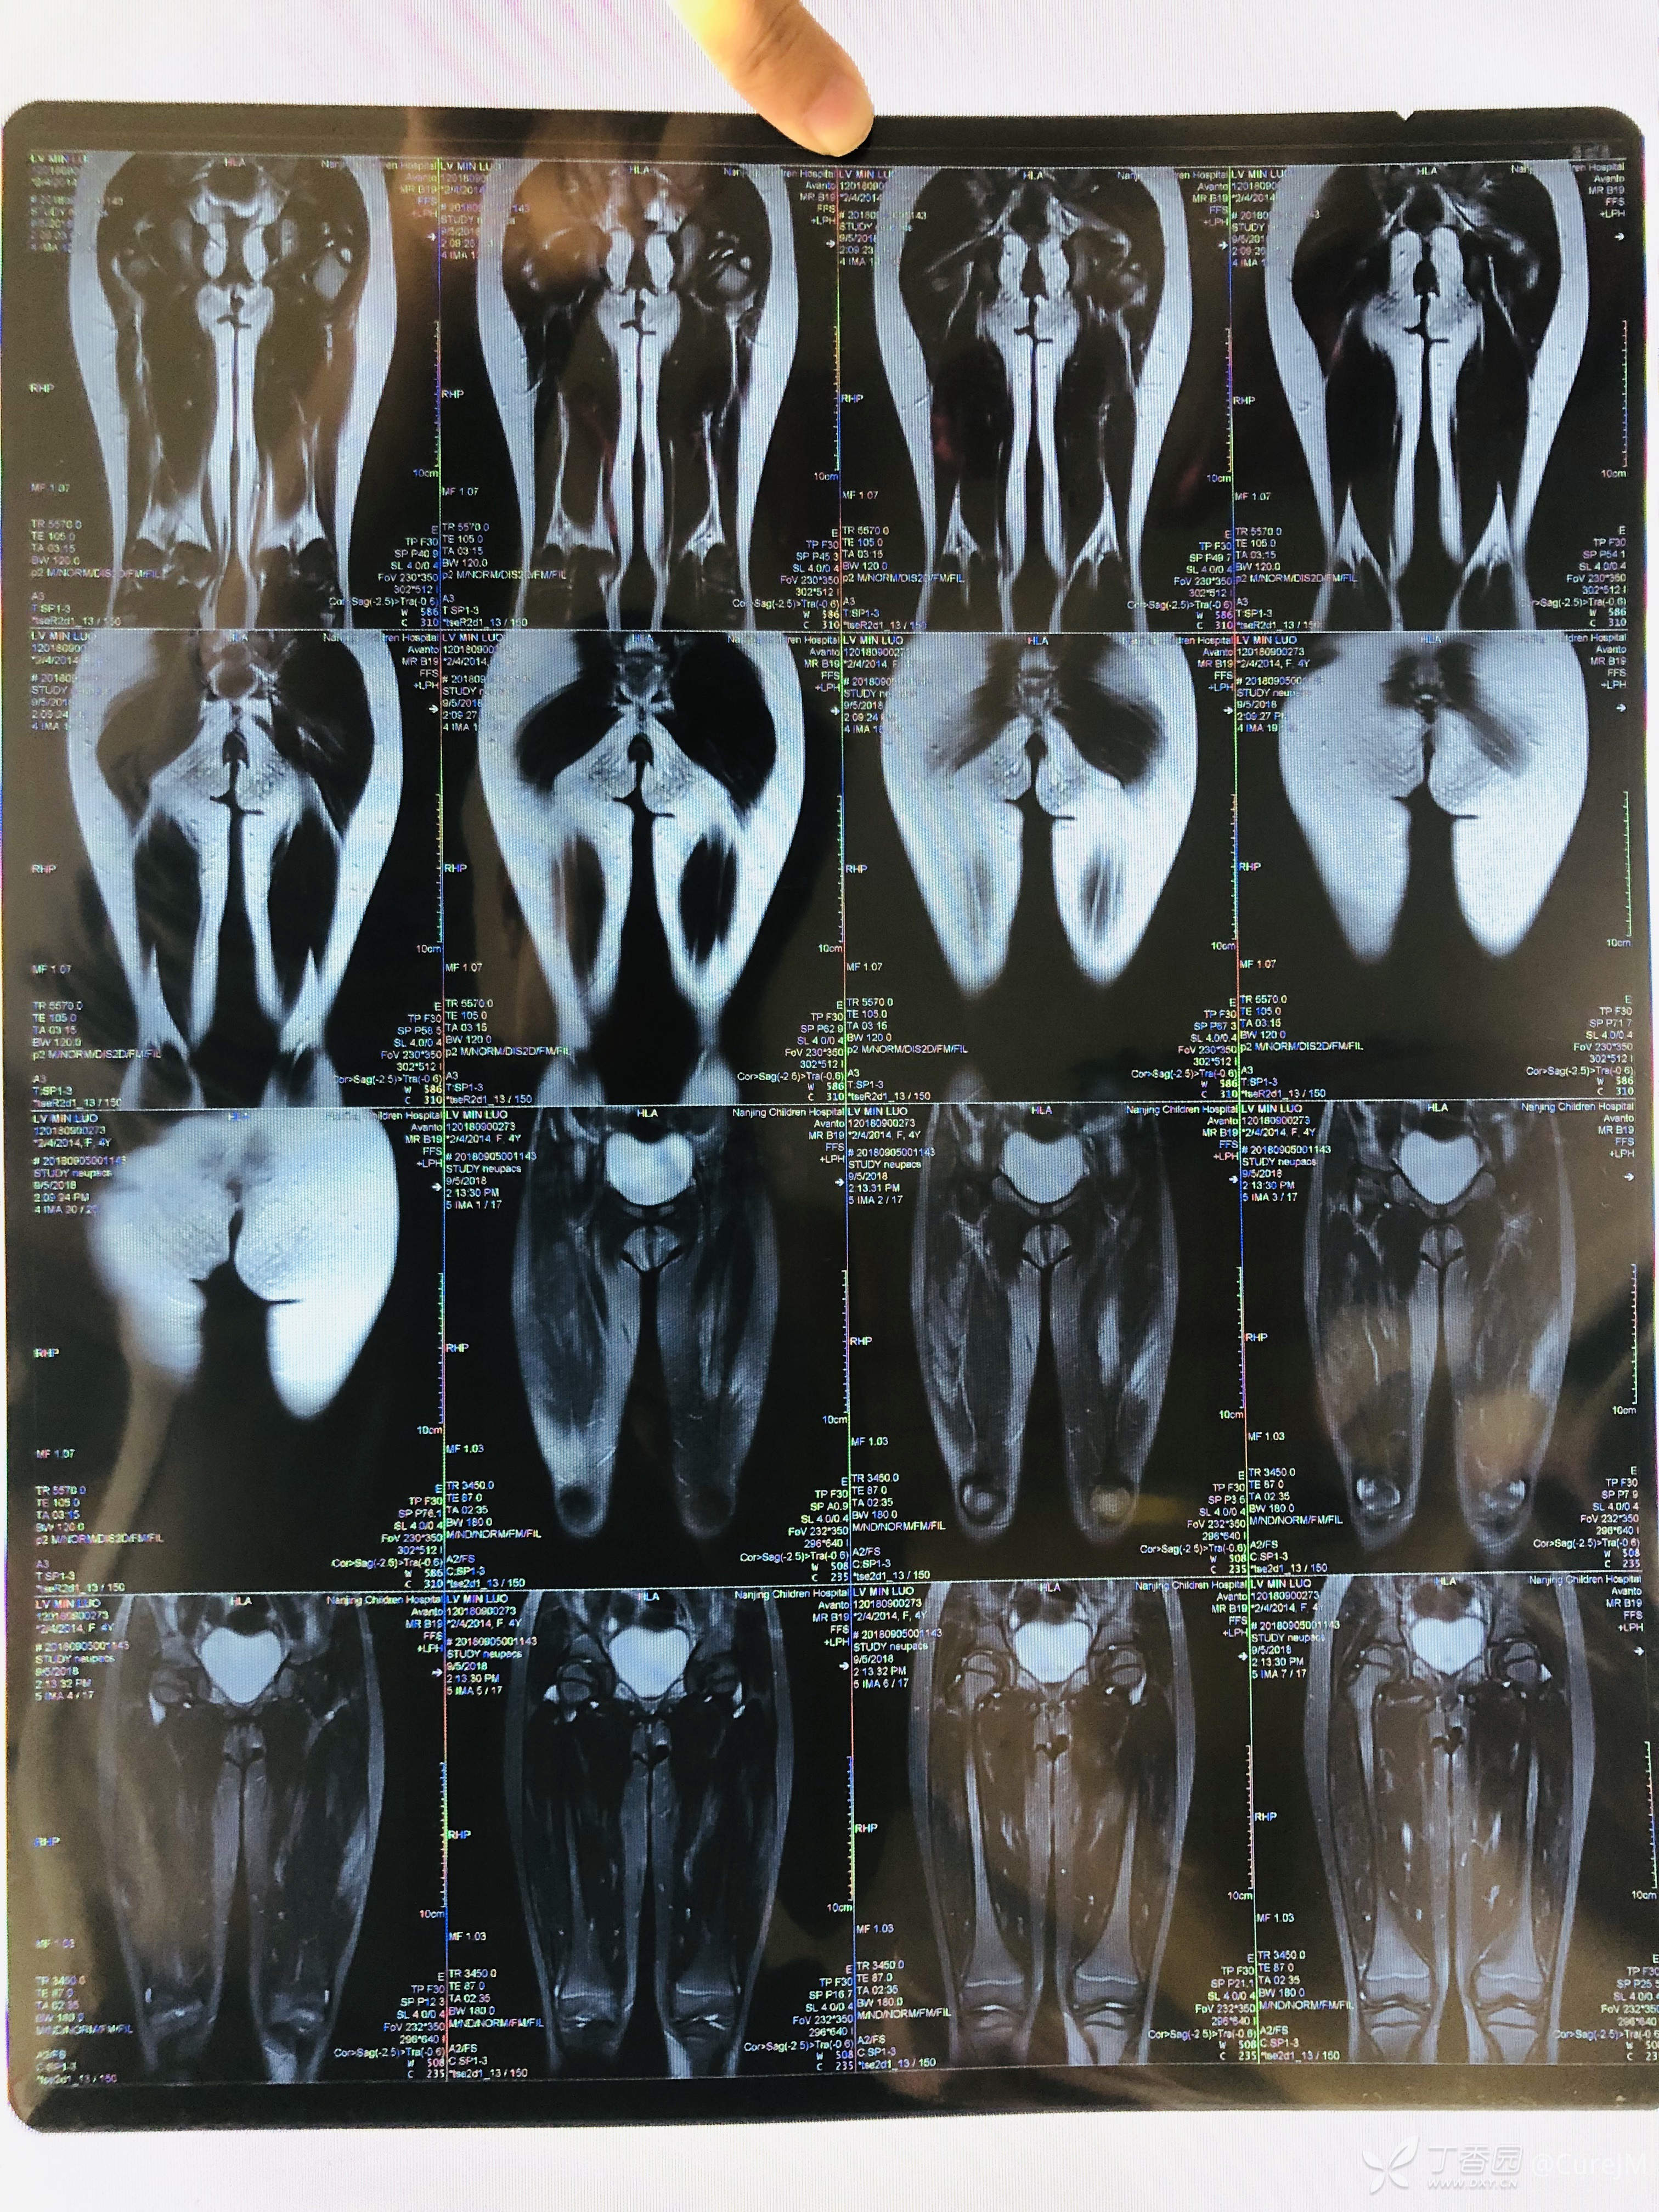

MRI平扫结果两侧髋部及大腿肌肉组织内水肿

1、诊治方案:予完善血尿粪常规、生化、心肌酶、自身抗体、肌炎抗体、肌电图、肺功能、胸部CT、双股骨MR 等相关检查,健康宣教已执行。